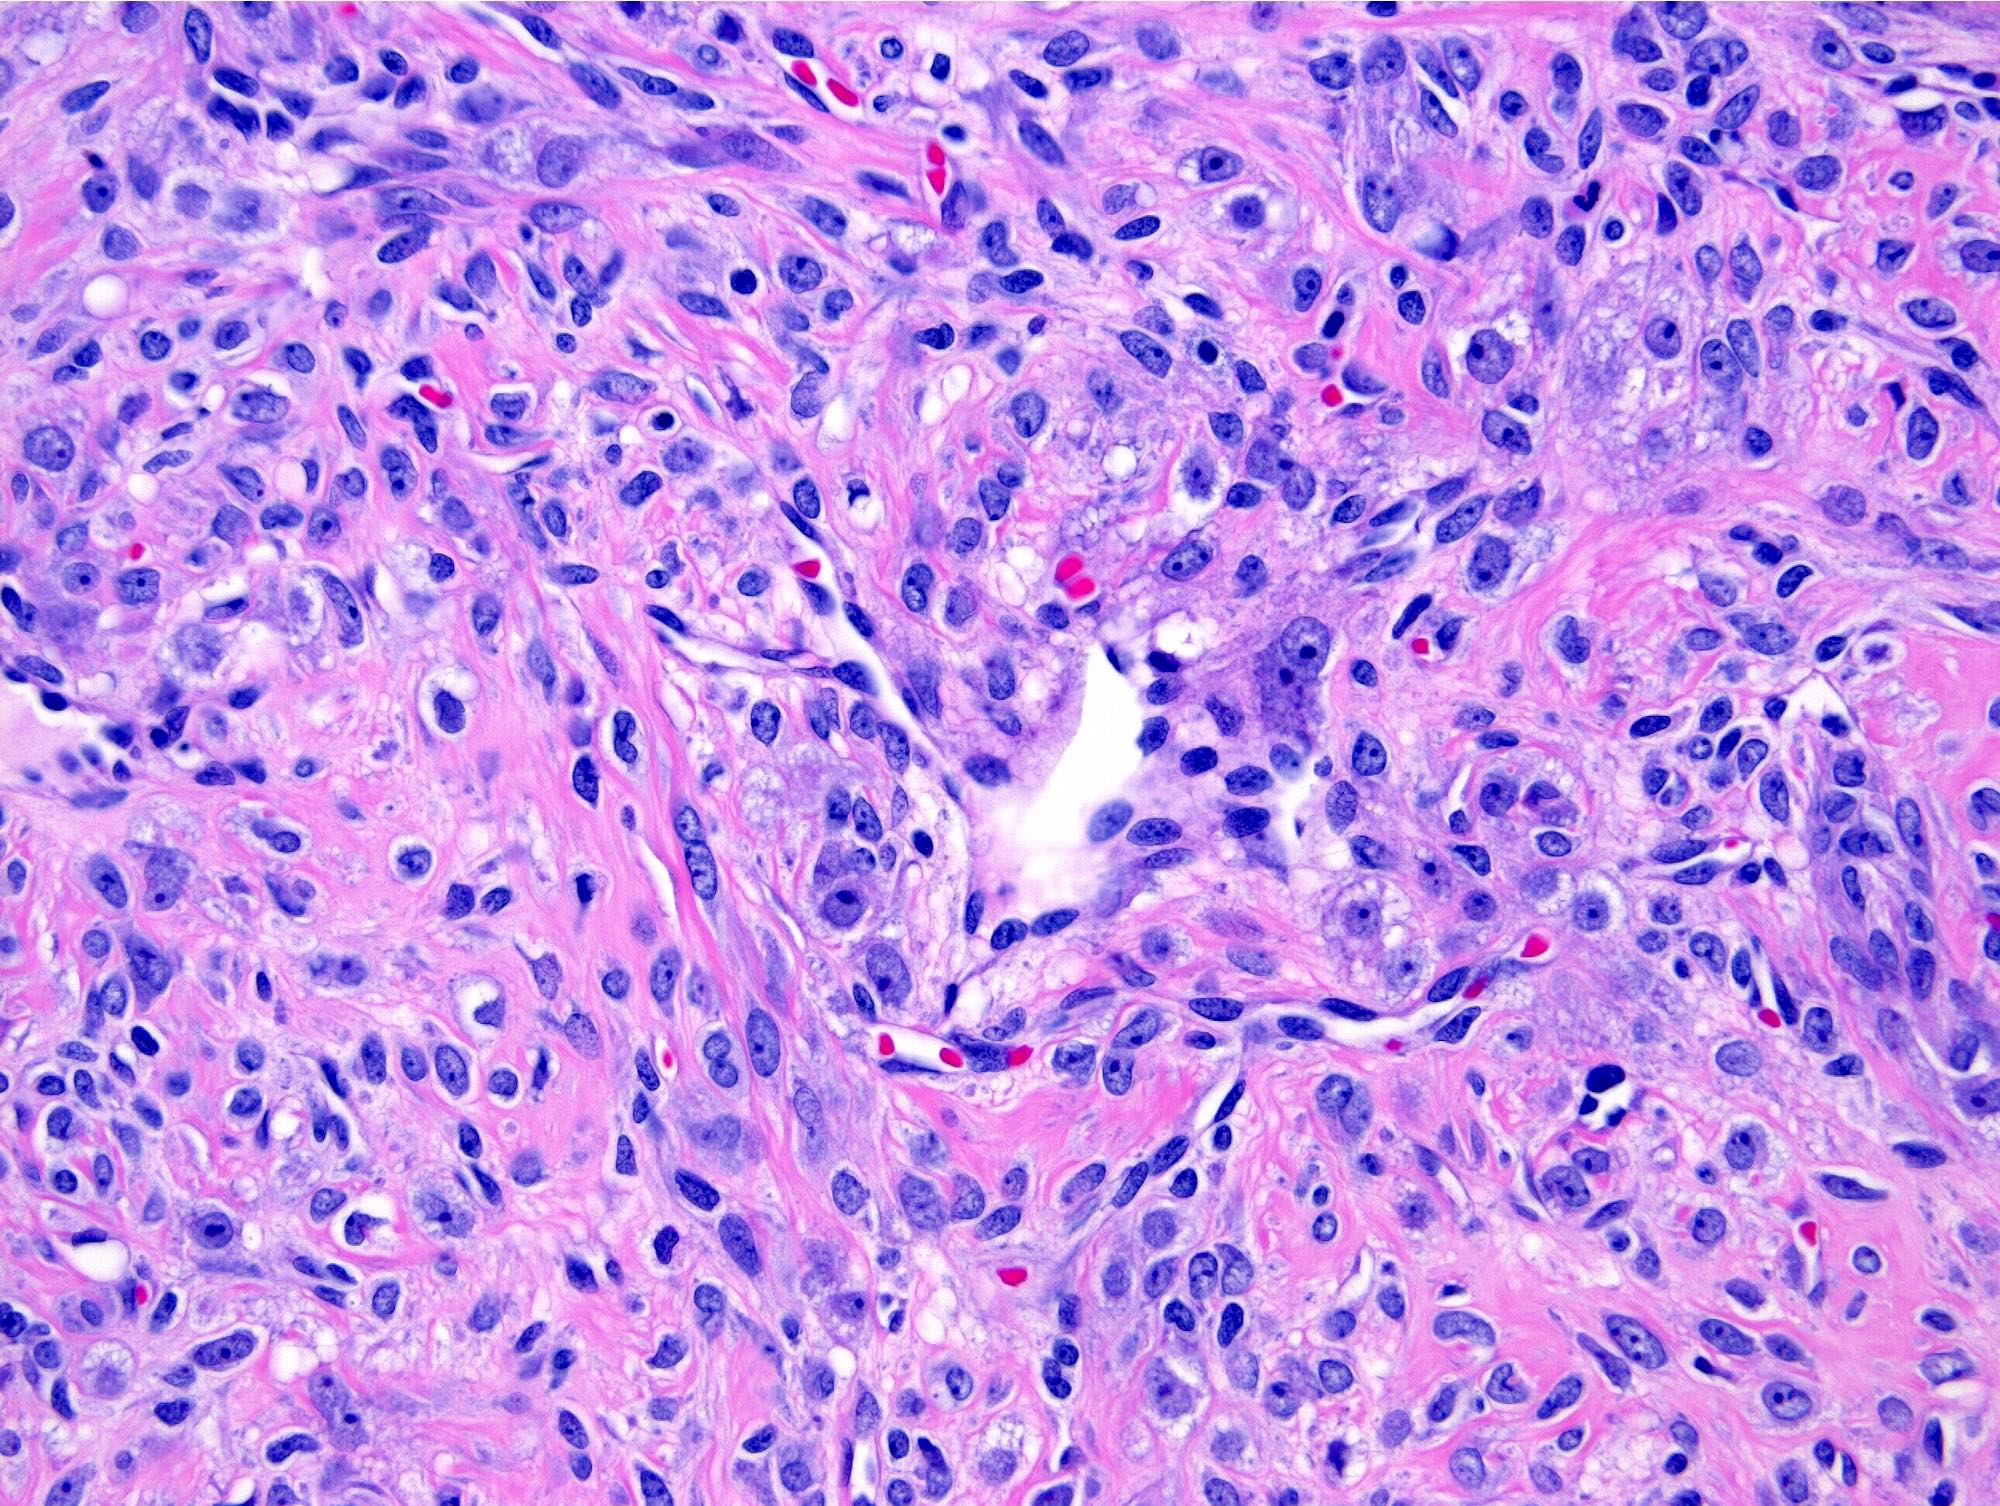

- Thin, dilated and branching hemangiopericytoma-like vasculature is often conspicuous in both components

- Pseudolobules comprised of a jumbled admixture of epithelioid (lutein) and spindled cells with minimal atypia

- Epithelioid cells: round nuclei with prominent nucleoli, vesicular chromatin and clear to vacuolated cytoplasm

- Occasionally have a signet ring-like appearance

- Spindled cells: elongated nuclei with indistinct nucleoli, bland chromatin and scant eosinophilic cytoplasm

- Mitoses are often inconspicuous but rarely can be up to 12/10 high power fields, no atypical forms (Int J Gynecol Pathol 2016;35:549)

- References: Cancer 1973;31:664, Histopathology 2022;80:360

Microscopic (histologic) images